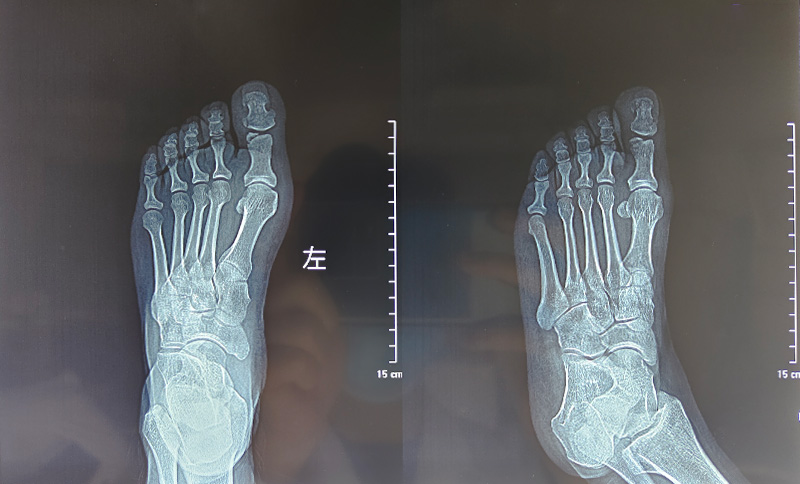

另一个病例是一位43岁的女性患者。因意外砸伤,导致左侧拇趾疼痛肿胀30分钟来院就诊。经详细检查,诊断为“左侧拇趾趾骨骨折”。骨三科医护团队在局部麻醉下,为其顺利开展了“左侧拇趾趾骨骨折闭合复位内固定术”。手术创伤小、用时短,术后患者疼痛明显缓解,对治疗效果给予了高度认可。

术前